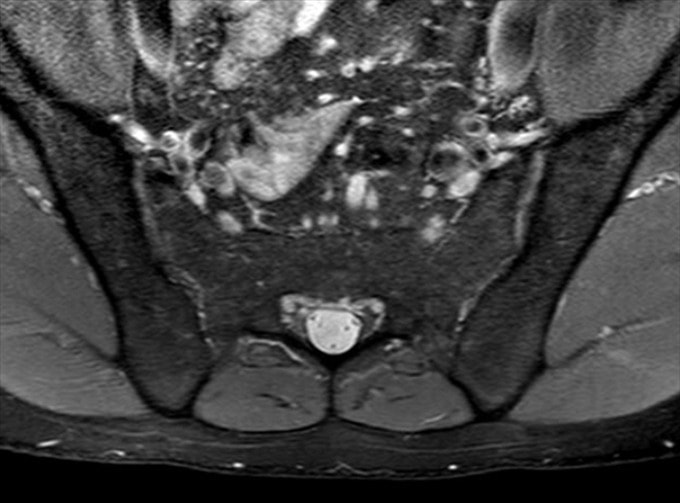

Avaliação das sacroilíacas pela RM

- Score Masei